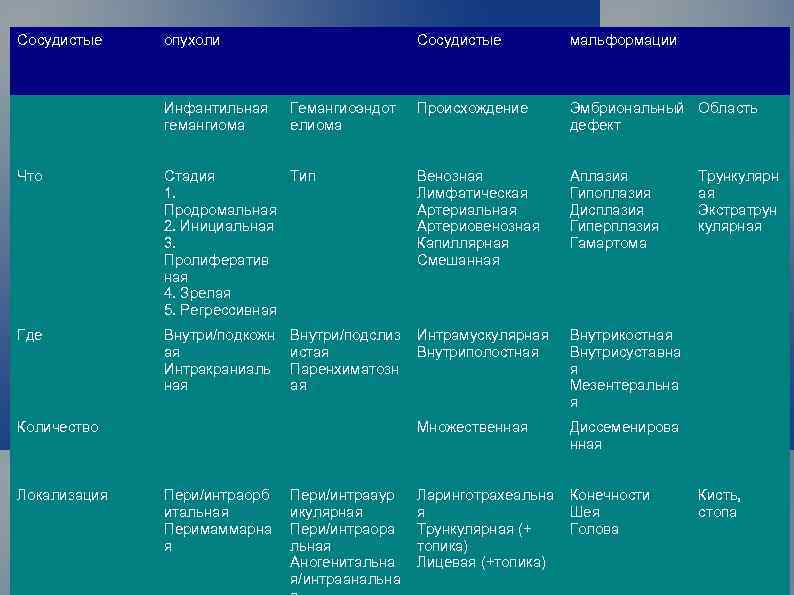

Сосудистые опухоли Инфантильная гемангиома Сосудистые Гемангиоэндот елиома мальформации Происхождение Эмбриональный Область дефект Что Стадия Тип 1. Продромальная 2. Инициальная 3. Пролифератив ная 4. Зрелая 5. Регрессивная Венозная Лимфатическая Артериальная Артериовенозная Капиллярная Смешанная Аплазия Гипоплазия Дисплазия Гиперплазия Гамартома Где Внутри/подкожн ая Интракраниаль ная Интрамускулярная Внутриполостная Внутрикостная Внутрисуставна я Мезентеральна я Множественная Диссеменирова нная Внутри/подслиз истая Паренхиматозн ая Количество Локализация Пери/интраорб итальная Перимаммарна я Пери/интрааур икулярная Пери/интраора льная Аногенитальна я/интраанальна Ларинготрахеальна Конечности я Шея Трункулярная (+ Голова топика) Лицевая (+топика) Трункулярн ая Экстратрун кулярная Кисть, стопа